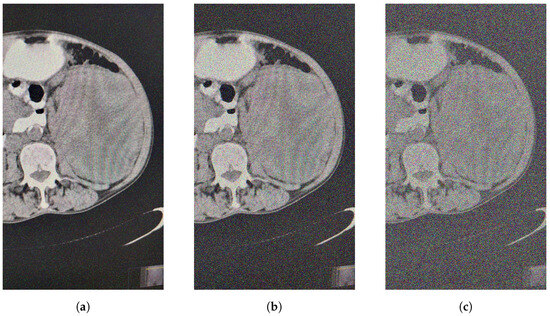

As we can see, the filtered image given below is contaminated with s p = 5 % , 10 % and 50 % salt and pepper noise. The chosen size of window is 5.

Let s p = 5 % (Figure 2).

Figure 2. (a) Contaminated image s p = 5 % . (b) Contaminated image s p = 20 % . (c) Contaminated image s p = 50 % .

Mathematics 12 02333 g002